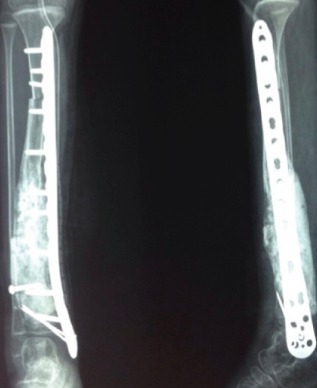

Limb preservation (salvage) surgery aims to remove malignant bone or soft tissue tumors while preserving the limb’s function and appearance, avoiding amputation in over 90% of cases today. Performed after neoadjuvant chemotherapy, it involves wide tumor resection with clear margins, followed by reconstruction.

Endoprosthesis (Megaprosthesis): Custom or modular metal implants replace resected bone/joint, ideal for peri-articular tumors.